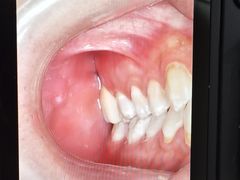

• 牙博士口腔品牌连锁(杨浦店)

• -牙博士口腔品牌连锁(杨浦店)